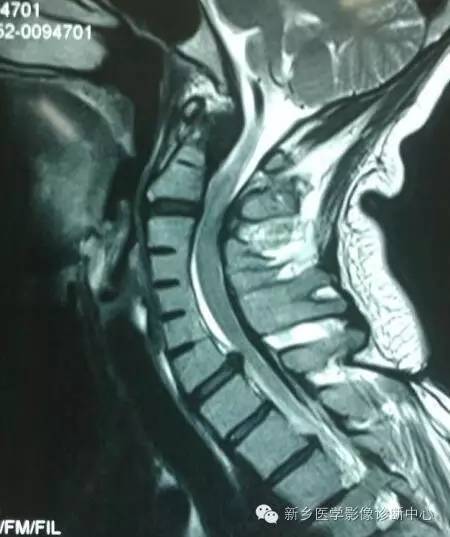

Klippel-Feil综合征就是由于基因突变或者其它因素作用下,引起的分节与再分节障碍所导致,一般分为 3种类型:Ⅰ型,为多个颈椎椎体融合;Ⅱ型,为仅1~2个椎间隙相邻的椎体发生融合;Ⅲ型,为颈椎融合同时合并胸段或腰段椎体的融合畸形。